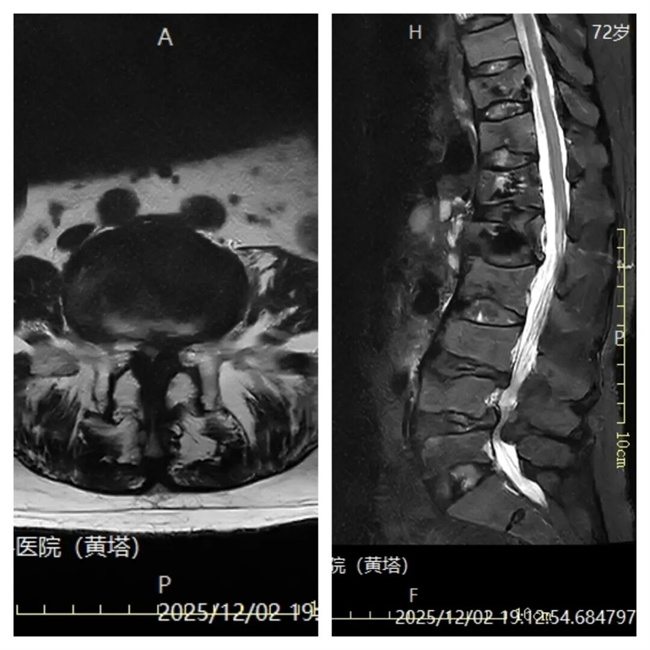

二、患者李某某,女,72岁,患者腰部疼痛伴双下肢麻木半月余,久坐、久行及劳累后症状加重,活动受限。为求进一步治疗,来到我院请专家会诊,通过各位专家会诊查体、查看影像资料并细致认真的分析后,意见:转脊柱科行微创手术治疗。